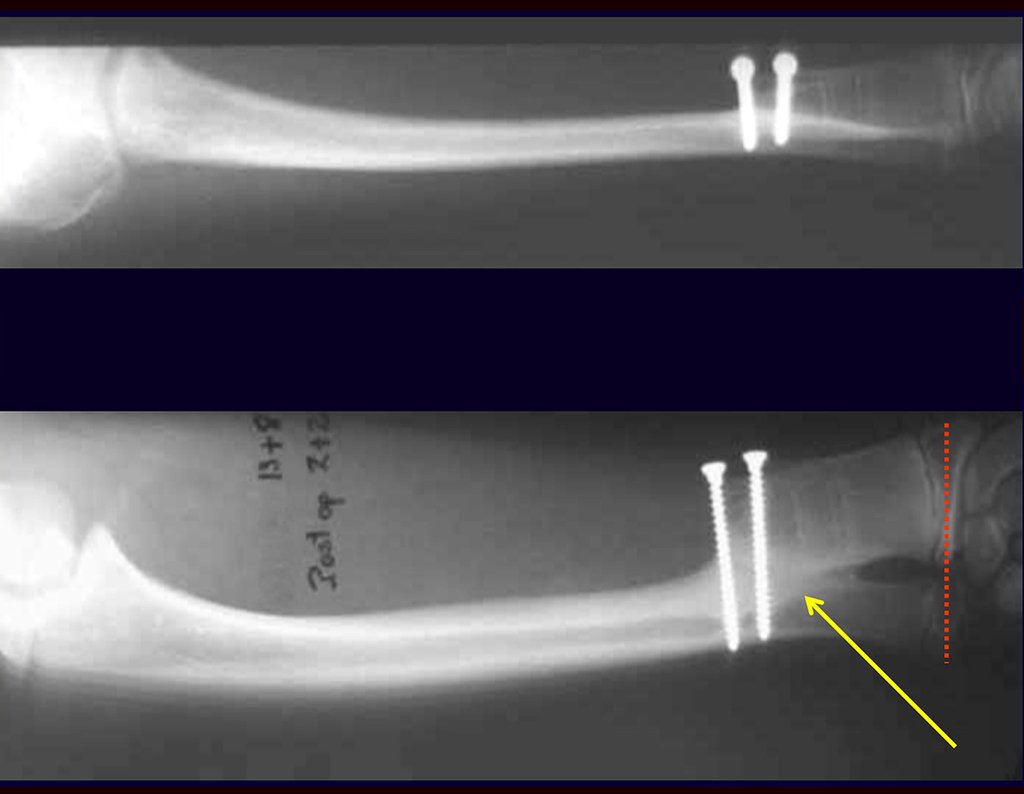

Es importante recordar el concepto de reparación de defectos óseos con injertos óseos: EN UNA RECONSTRUCCIÓN BIOLÓGICA, TODO INJERTO ÓSEO COLOCADO PARA LLENAR CAVIDADES O FALTAS SEGMENTALES PASA POR UNA FASE DE REABORTO PARA POSTERIOR REINTEGRARSE , REPARANDO LA PÉRDIDA ÓSEA. El injerto debe estar entrelazado y sobrepasar el nivel de la osteotomía, evitando pseudoartrosis, como ejemplifica este caso de condrosarcoma en las figuras 36 a 38, flechas azules.